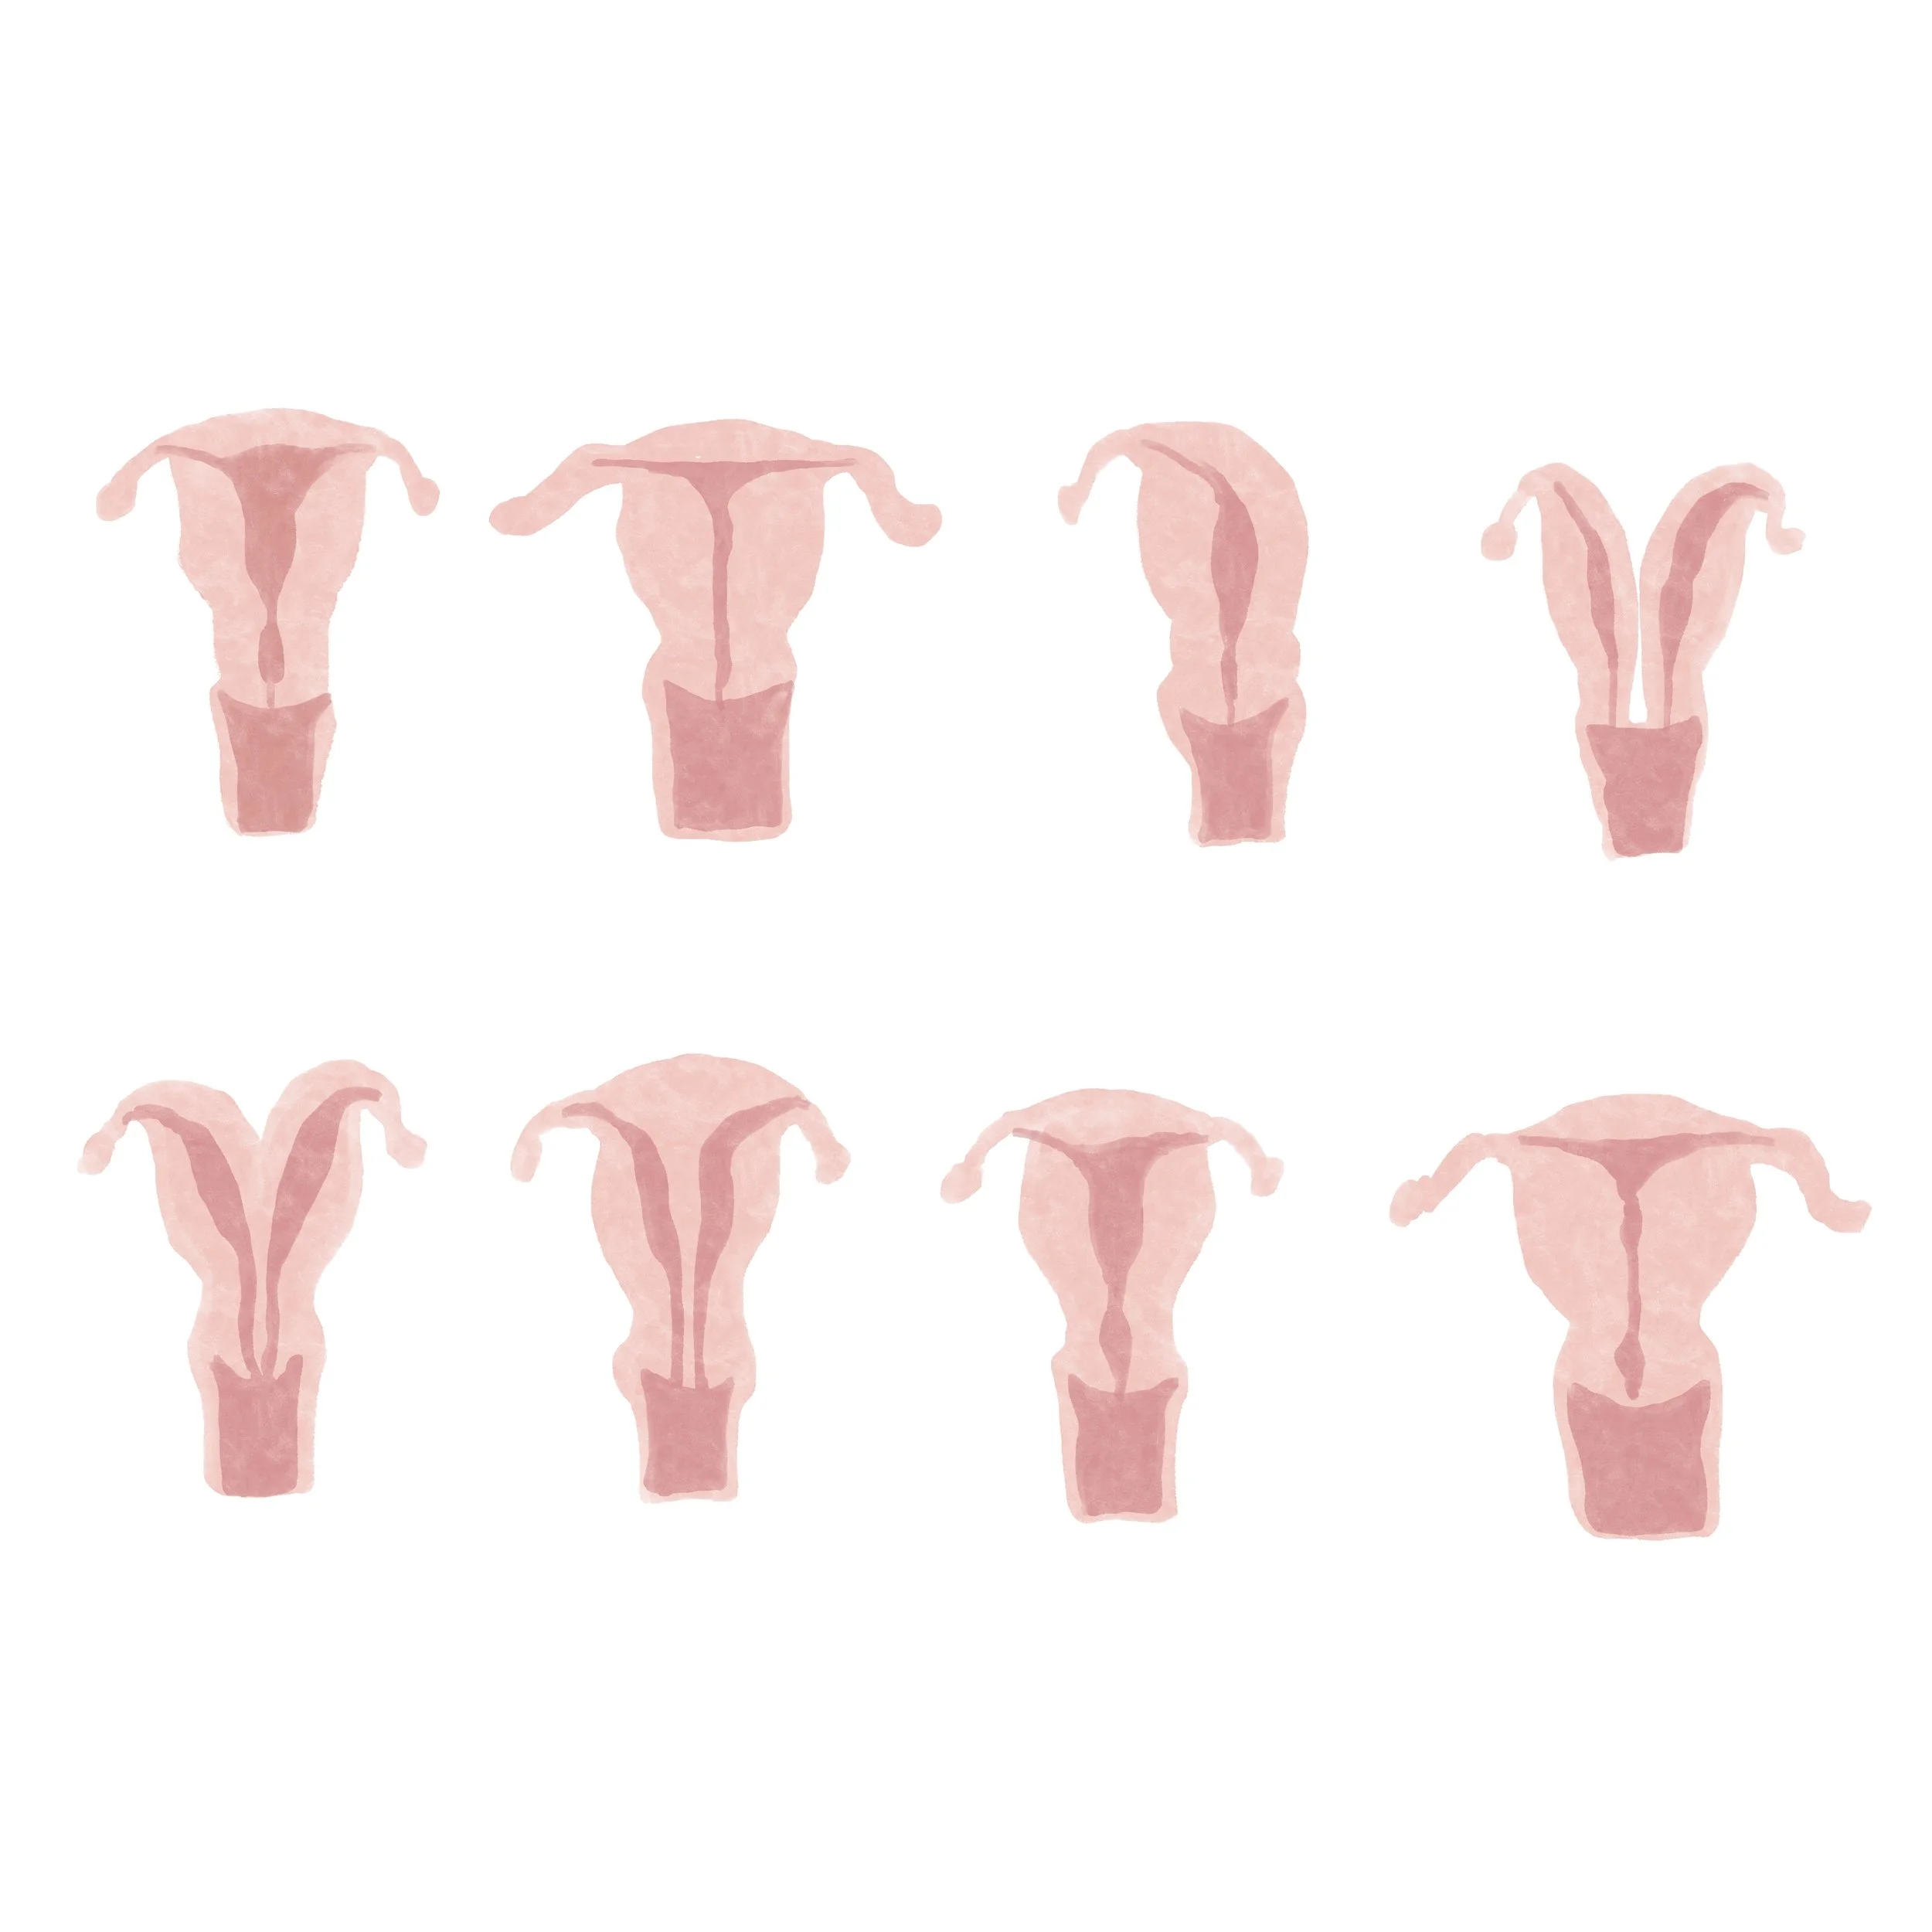

I created watercolor-style digital illustrations for an educational series on reproductive health called “How to Start a Family” for parents.com.

Digital watercolor artwork, 2022.

Uterine Malformations